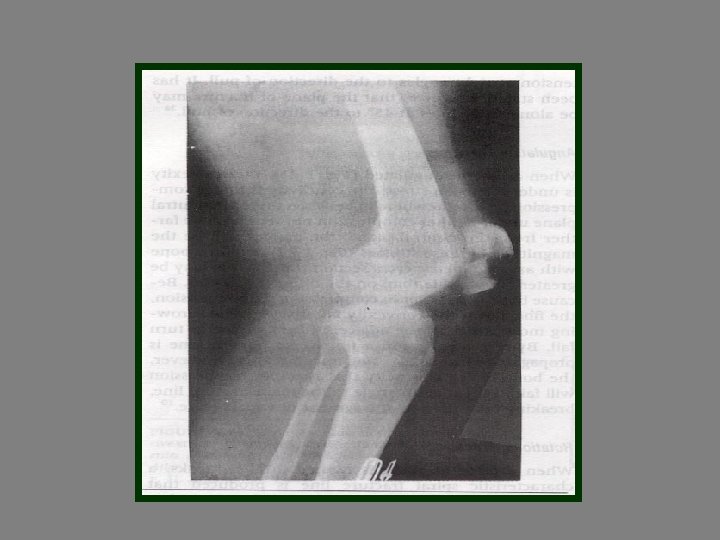

Fracture paterns Hair line Fr Transvers Fr Depress Fr Oblique Fr Spiral Fr Green

Fracture paterns Hair line Fr Transvers Fr Depress Fr Oblique Fr Spiral Fr Green stick Fr Cominuted Fr Compres Fr Segmental Fr Epiphyseal Fr Impacted Fr